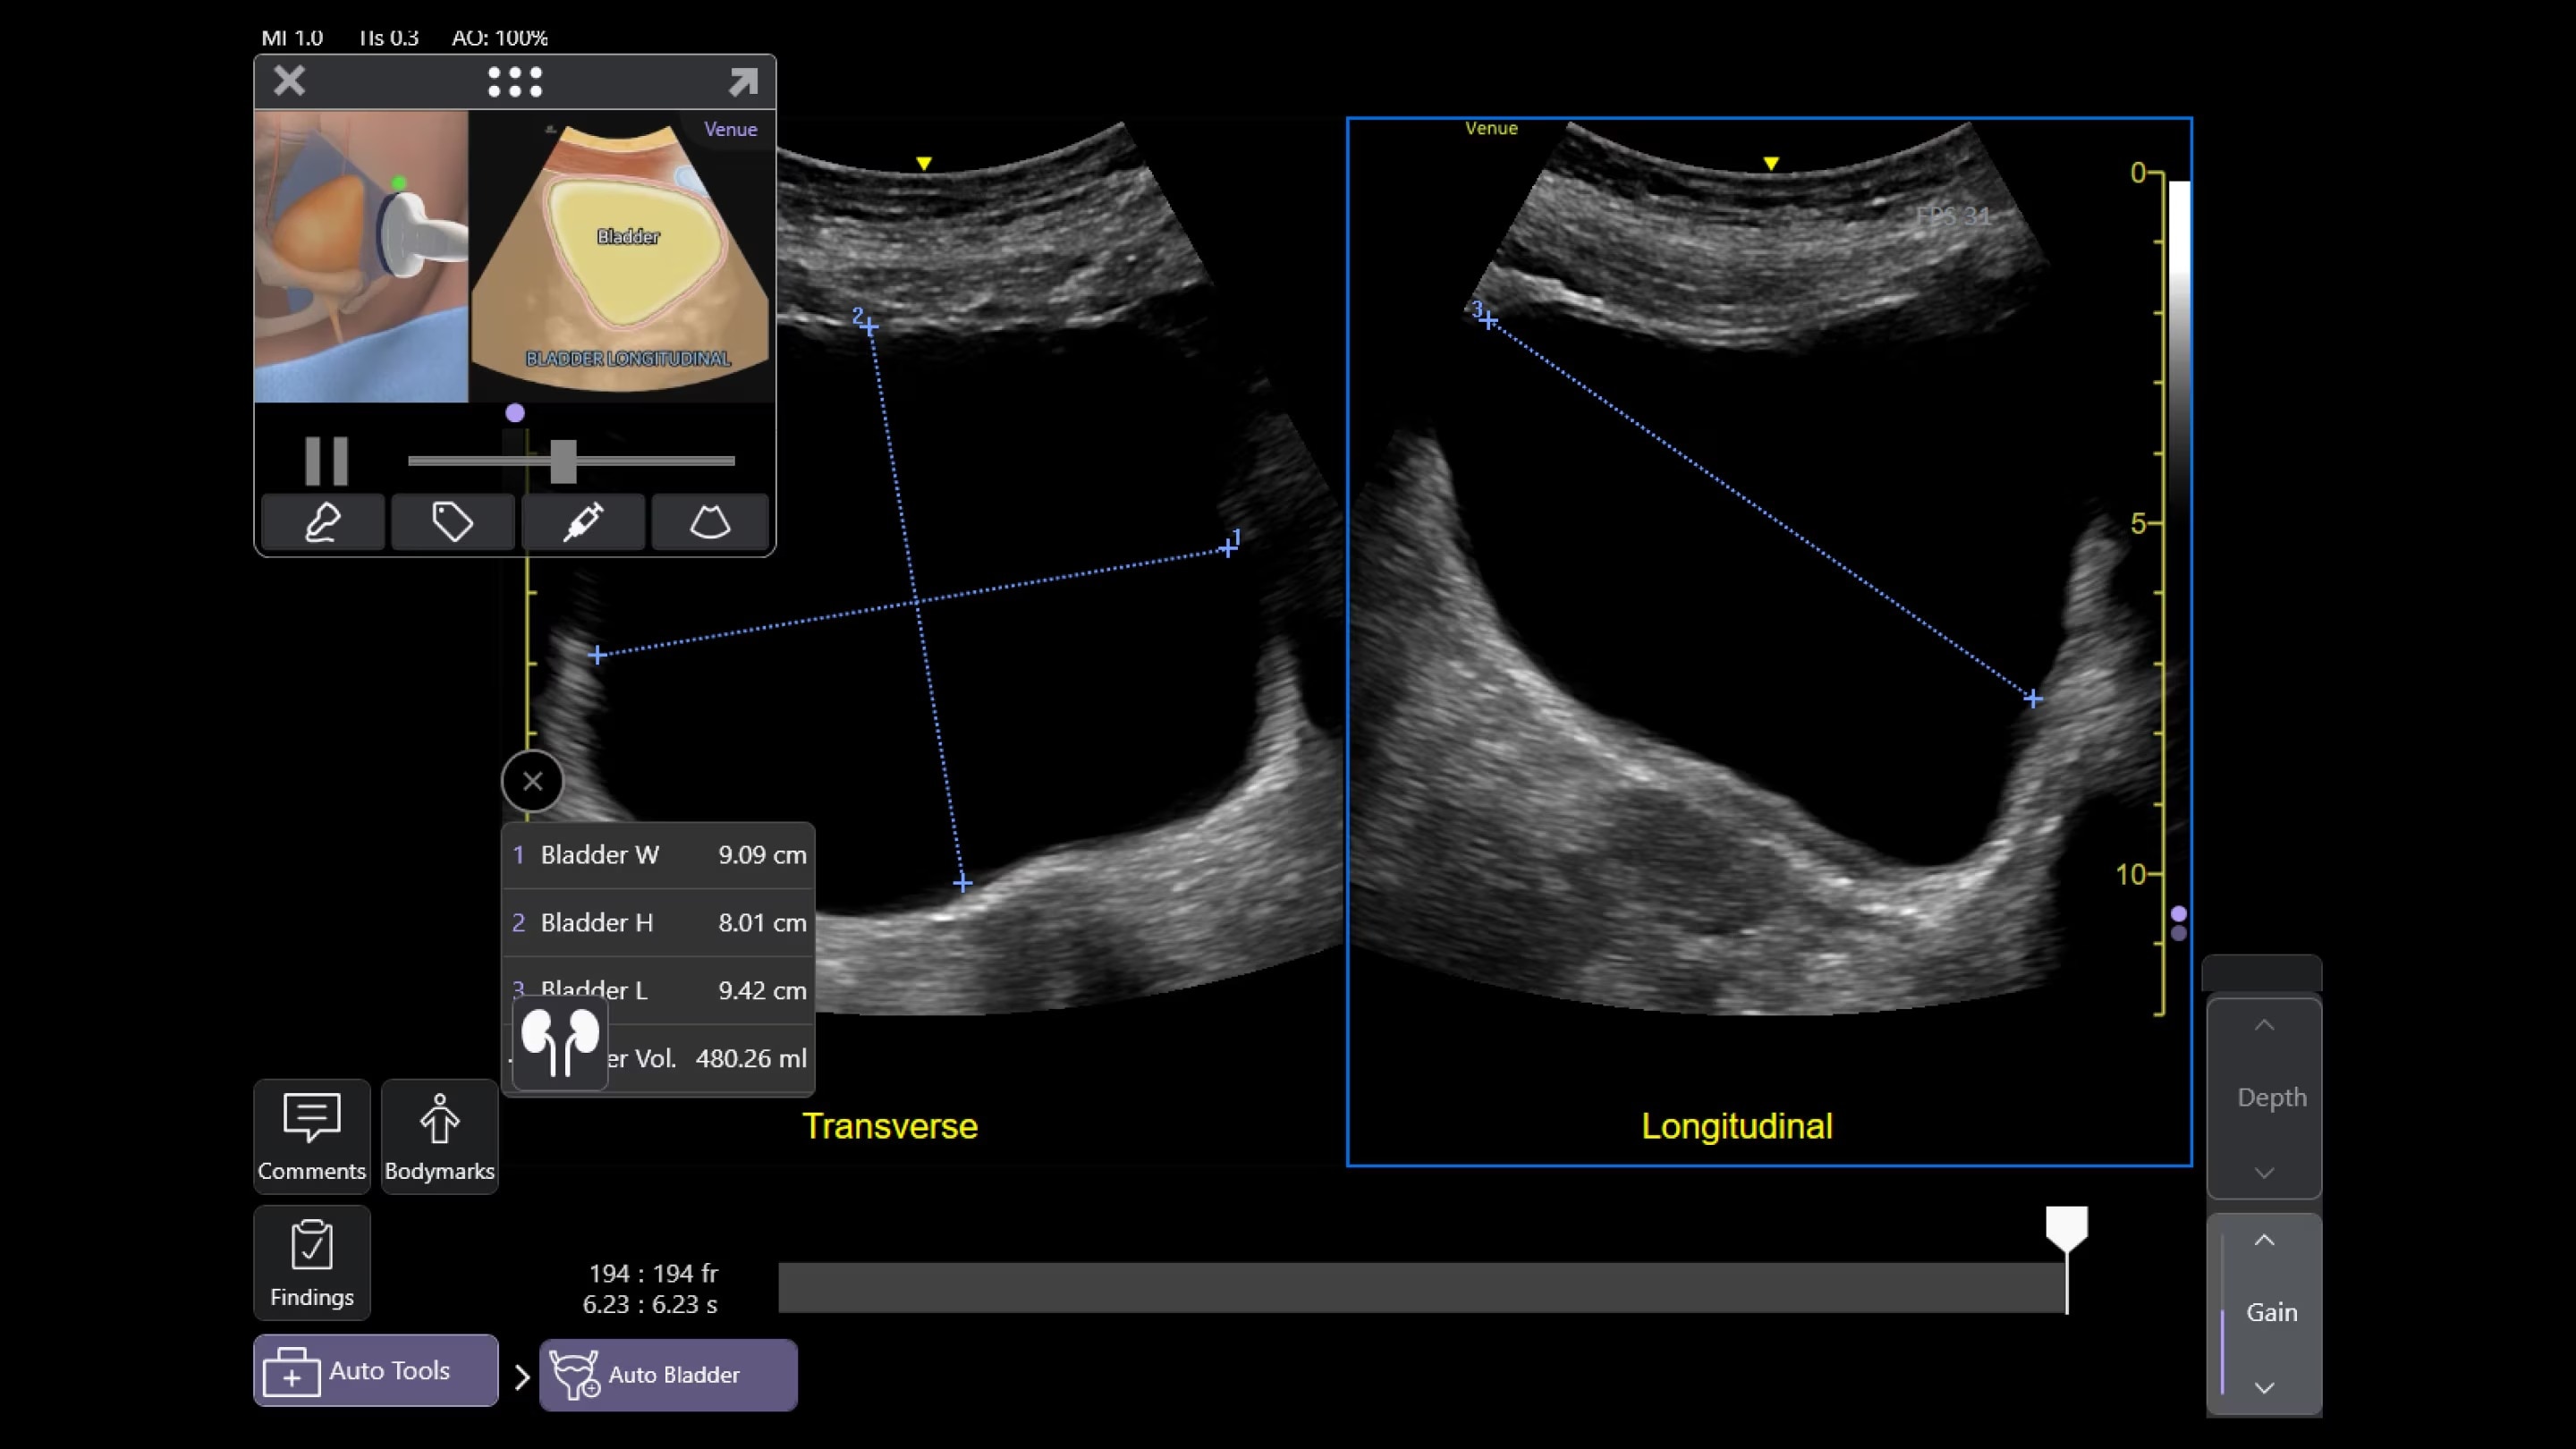

AI-enabled Auto Bladder Volume

Auto Bladder Volume provides rapid and easy urinary bladder volume measurements, saving clinicians valuable time and enhancing clinical accuracy. It measures bladder dimensions and calculates the bladder volume from two views: transverse and longitudinal.